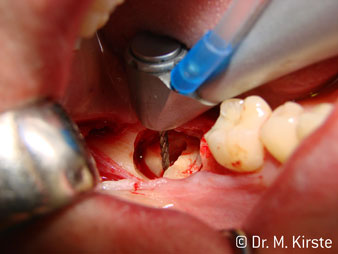

45° açılı angldruva geniş avantaj yelpazesi sebebiyle özellikle seçildi. Bu enstrümanın geliştirilme nedeni olan cerrah meslektaşlarım angldruvaların kısıtlı alanlardaki çalışma yeteneğini yakında takdir edeceklerdir. Özellikle gömük diş çekimlerinde (res. 2) yumuşak dokunun yanak bölgesine doğru yarılmasına gerek kalmaz(res. 3). Angldruvanın kafa dizaynı sayesinde retromolar bölgede hızlı ve güvenli çalışma sağlar.

Angldruva kafası içindeki profesyonel tasarımlı dişliler frezin sessiz çalışmasını garanti eder; kök separasyonu yapılırken atravmatik operasyona olanak verir. (res. 4-9).

Fig. 3

Fig. 5